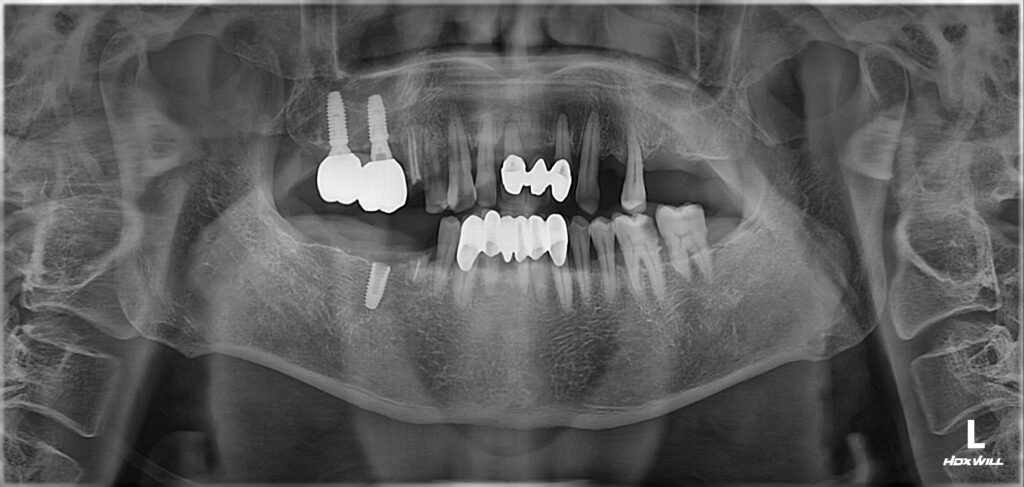

50대 남성분께서 치아가 없어서 식사를 못하신다며 임플란트 치료를 위해 치과에 내원하셨습니다.

우측아래(사진상 왼쪽 아래)와 좌측 위(사진상 오른쪽 위) 치아가 없어서 어금니로 식사를 못하시는 상태였습니다.

뿌리만 남은 치아(빨간색 화살표)와 염증으로 흔들리는 앞니는(연두색 화살표) 발치를 해야 하는 상황입니다.

발치를 하고 임플란트를 해서 어금니로 식사를 할 수 있도록 그리고 앞니는 발음과 심미의 기능을 수행할 수 있도록 해줘야 할 것 같습니다.